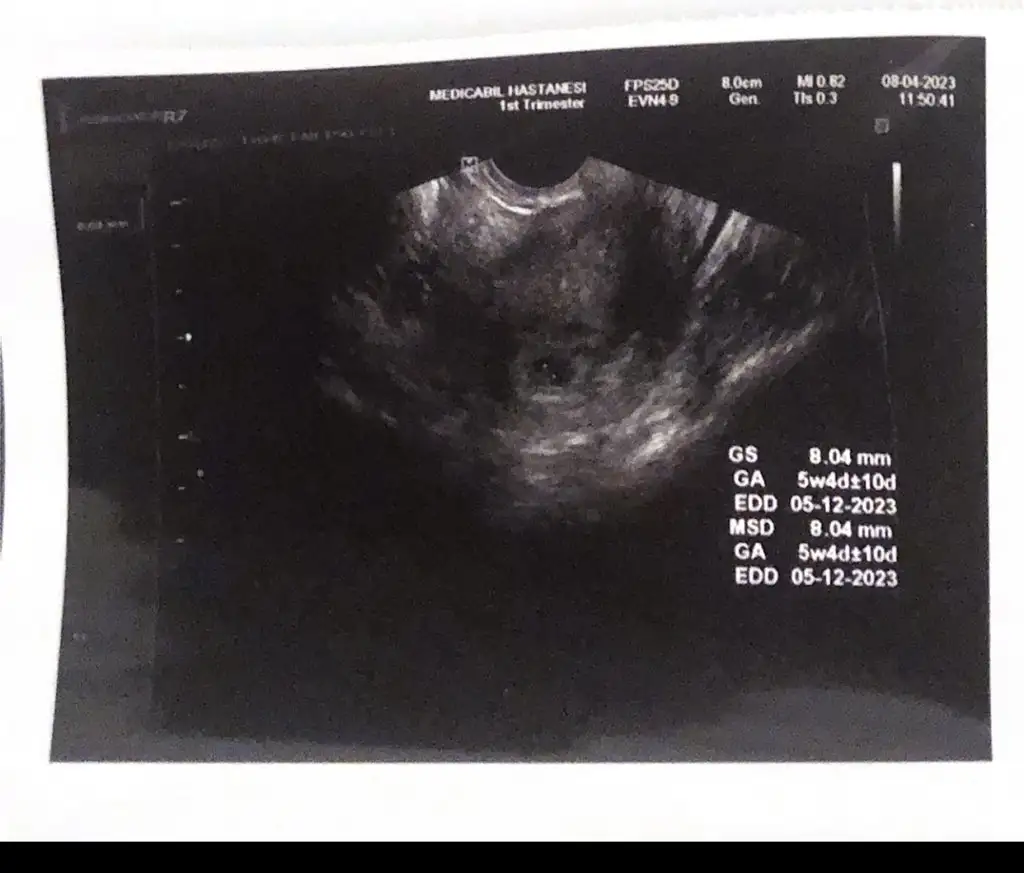

Hayırlı olsun canımKızlarrrr biz kesemizi gorduk elhamdülillah doktor gayet düzgün dedi 4 buçuk haftalikmis 15 gün sonra kalp atışını dinlemeye gel dedi bayramdan sonra inşallah şükürler olsun